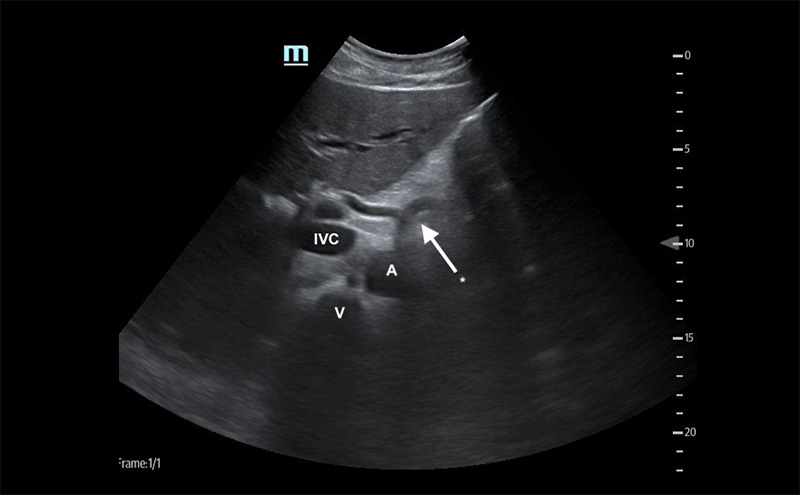

- With the transducer in the subxyphoid region, transducer in the transverse plane, evaluate the periaortic region for large lymph nodes. (Figure 1, #2)

- Identify the arch of the vertebral body in the far field then the aorta just to the patient’s left.

- Identify the “seagull sign” of the celiac trunk and slide the transducer inferiorly to the bifurcation of the common iliac arteries.

- Normally, lymph nodes will be difficult to visualize because they are small and normally hypoechoic with a hyperechoic central hilum. As they enlarge, the architecture is distorted, and they develop a homogeneous echotexture. Attempt to image lymph nodes in 2 planes and measure the diameter.

Figure 3. Proximal aorta (A) with celiac trunk "seagull sign" (*) adjacent to the IVC and vertebral body (V)